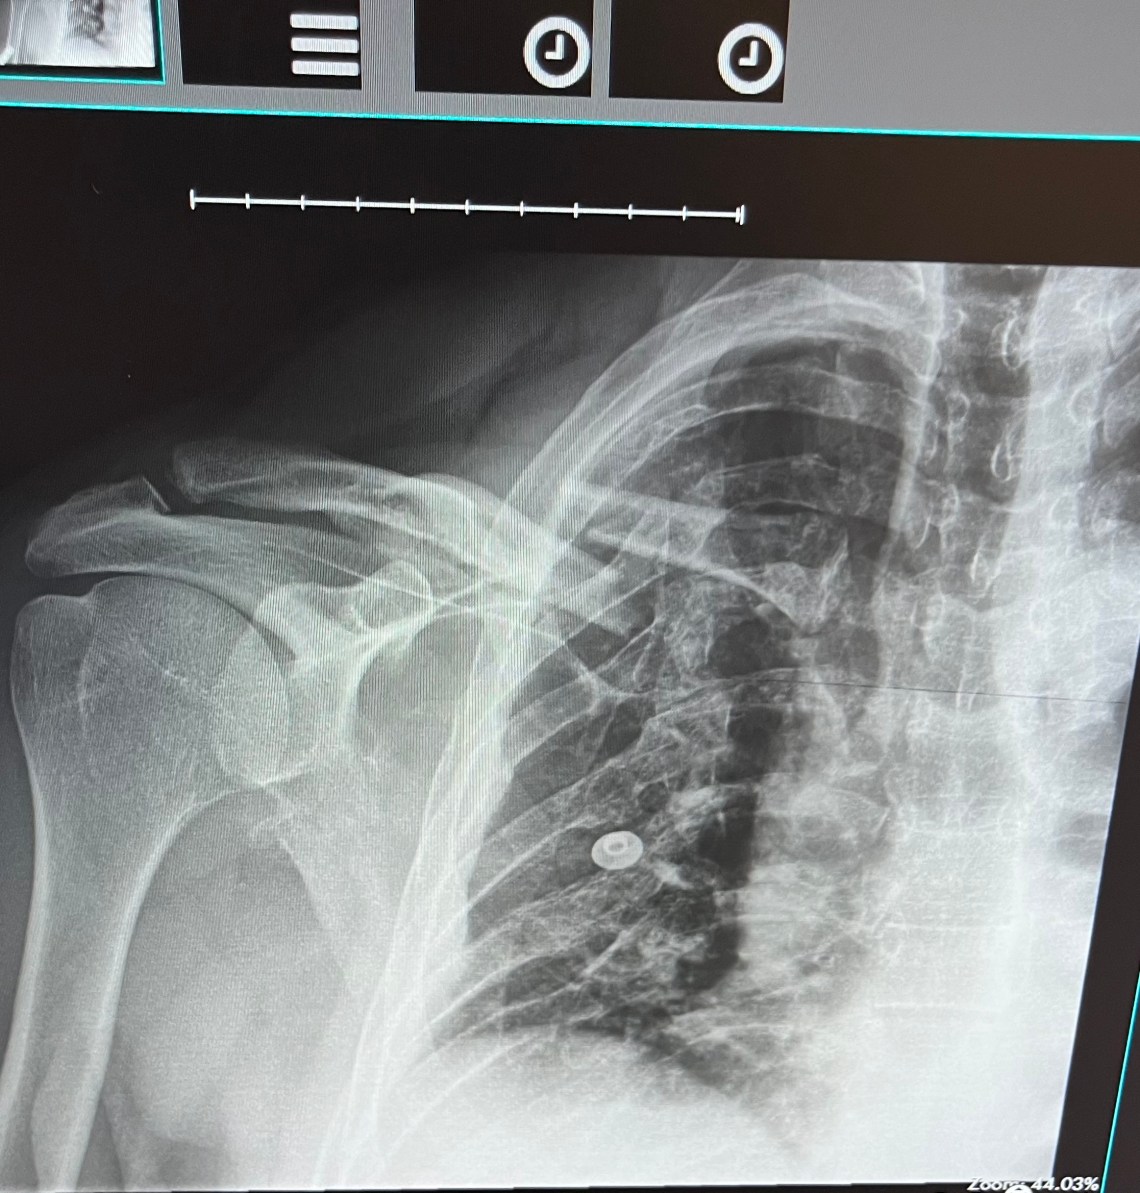

I had to pee. After my off, that evening in X-ray at UPMC, 331 milliliters worth. (Perversely, I took a picture (below). Moderate-yellow but not shockingly so. I rule out dehydration as a cause for any passing-out.